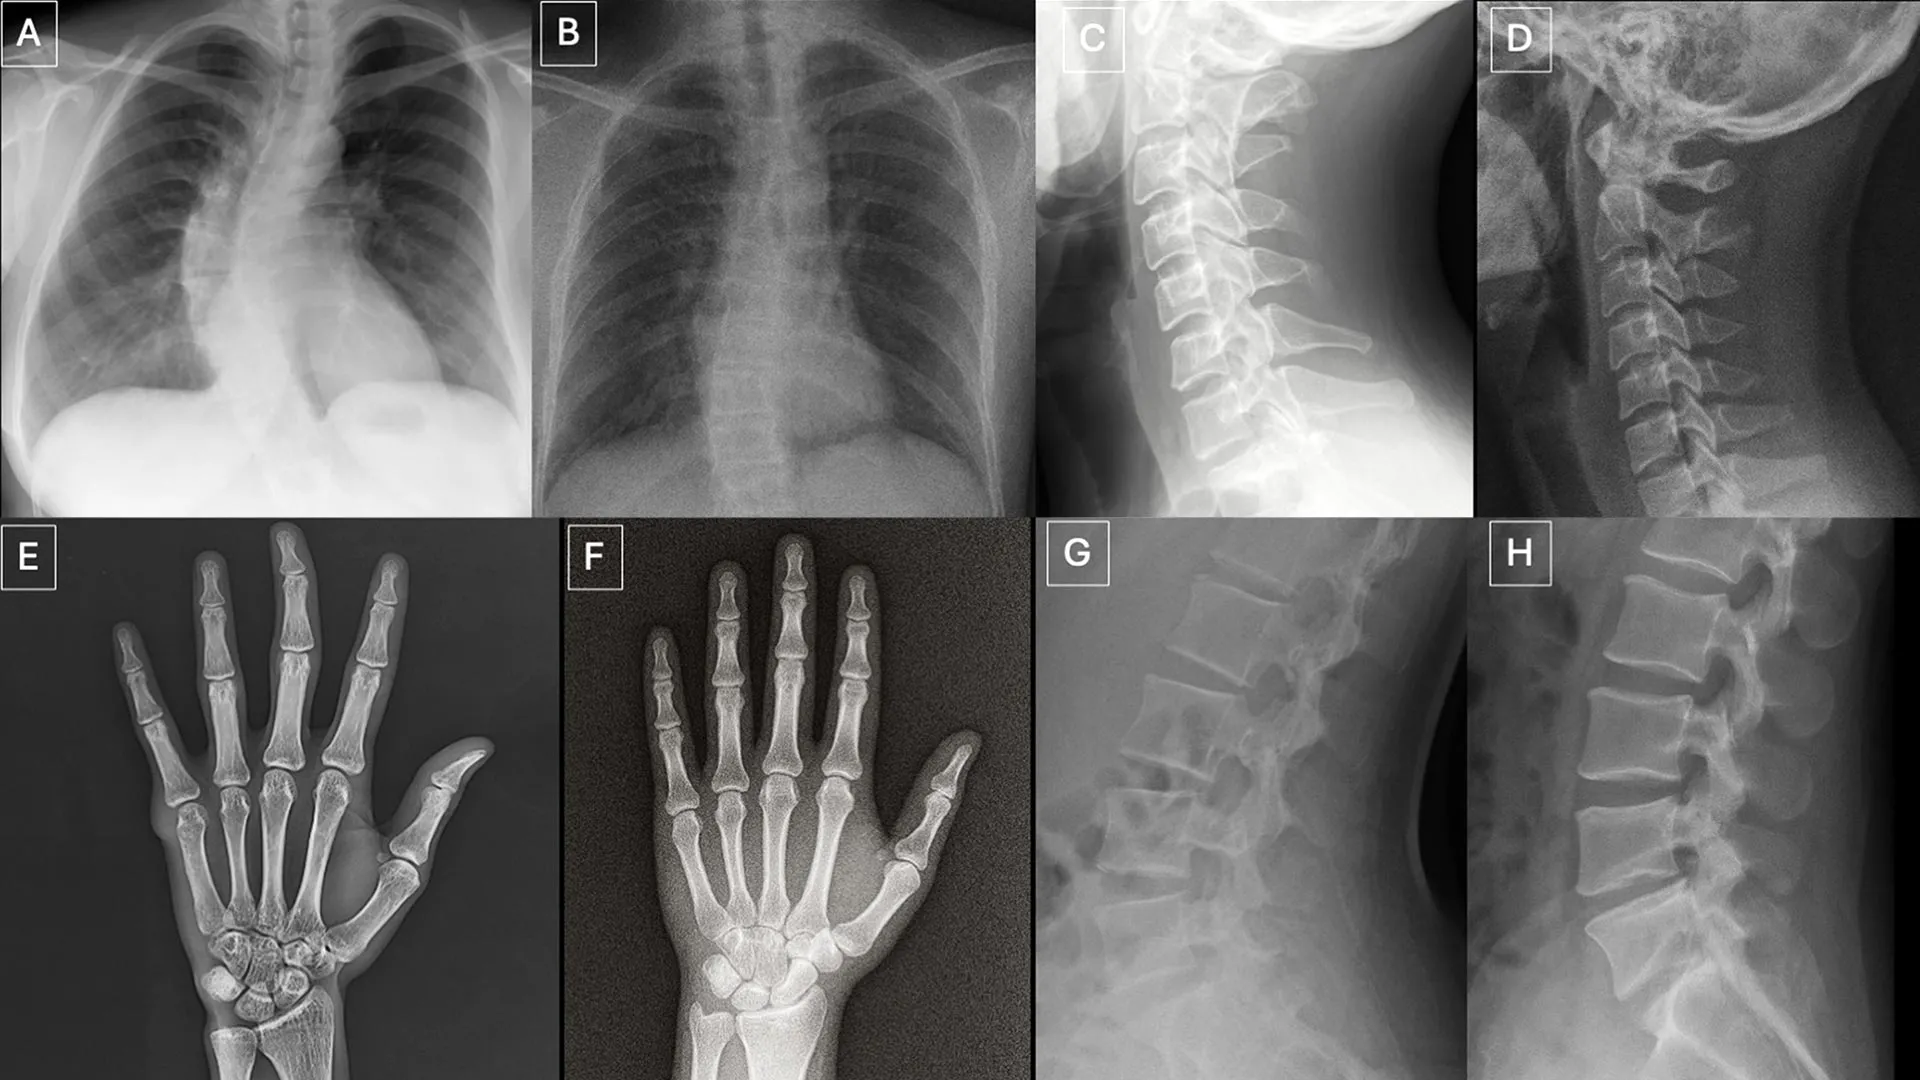

A new study published on March 24 in Radiology, the journal of the Radiological Society of North America (RSNA), shows that both radiologists and multimodal large language models (LLMs) have difficulty telling real X-rays apart from artificial…